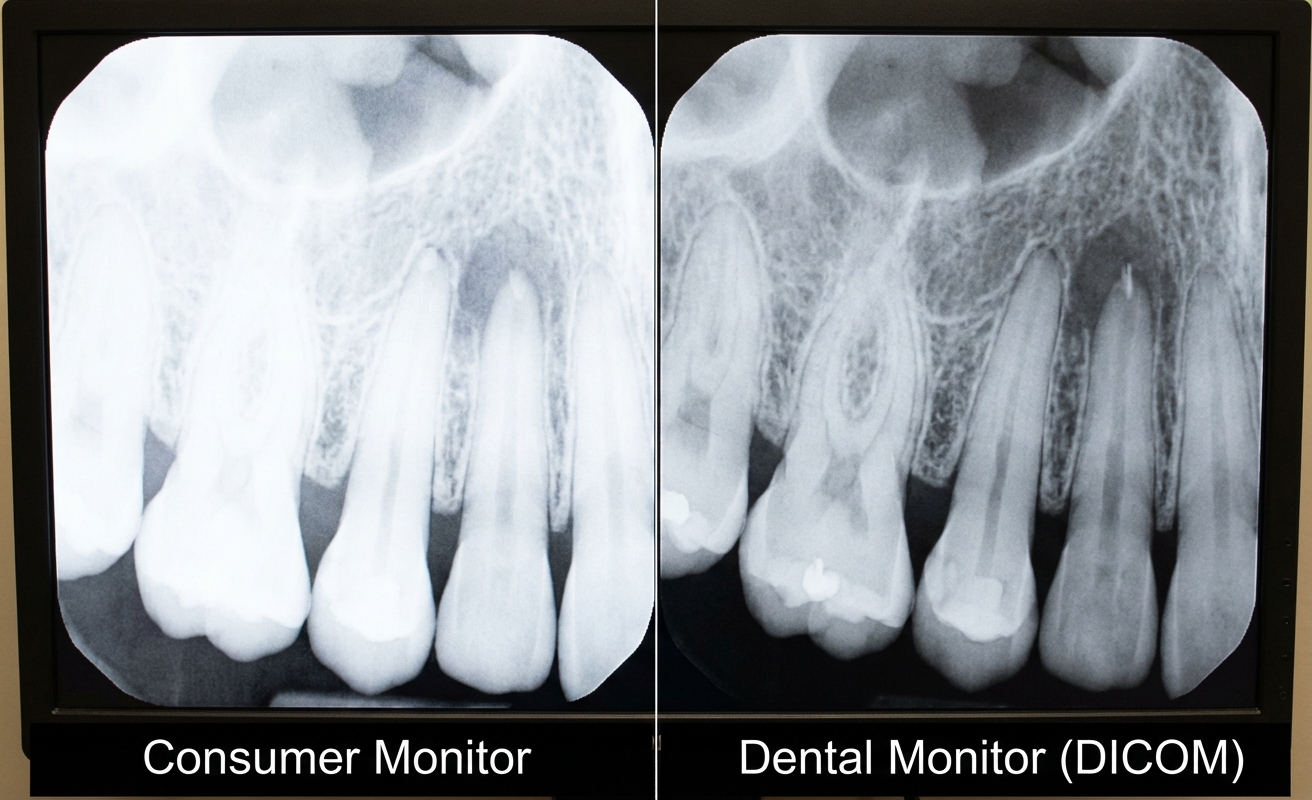

Dental imaging relies heavily on grayscale accuracy. Consumer monitors may display images differently depending on brightness settings, panel variation, or calibration inconsistencies. This can make it more difficult to interpret subtle differences in X-ray images.

Accurate image presentation is the foundation of dental imaging. Professional dental displays support DICOM Part 14 calibration, ensuring stable grayscale performance across different imaging scenarios.

This is essential for interpreting X-rays and CBCT scans where subtle variations can affect clinical decisions.